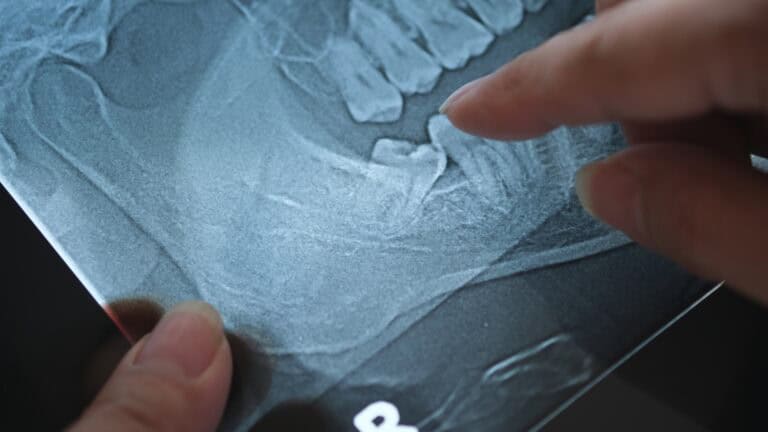

5 Signs You Need a Tooth Extracted

The thought of having a tooth pulled can be intimidating, but sometimes it is the most effective step toward protecting your long-term oral health. At...